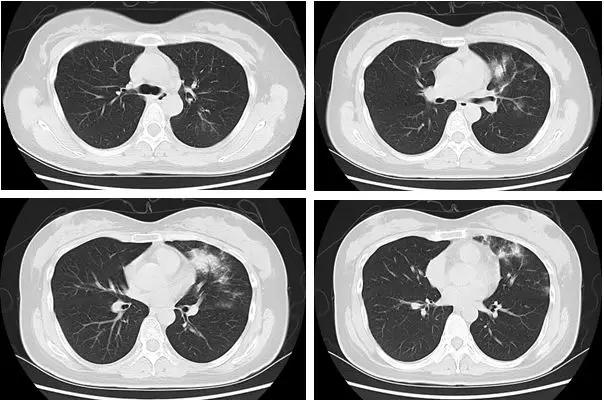

最为典型和有特征的早期表现:

胸膜下斑片状磨玻璃影,多发、单发都可以;其纹理可呈网格样(铺路石征)

1. 早期病变为局部斑片状亚段分布为主;

2. 进展期多个累及多个肺叶,并出现部分实变;

3. 重症期双肺弥散性实变」白肺」 ;

混合磨玻璃及晕征

支气管充气征

形态:扇形、球形